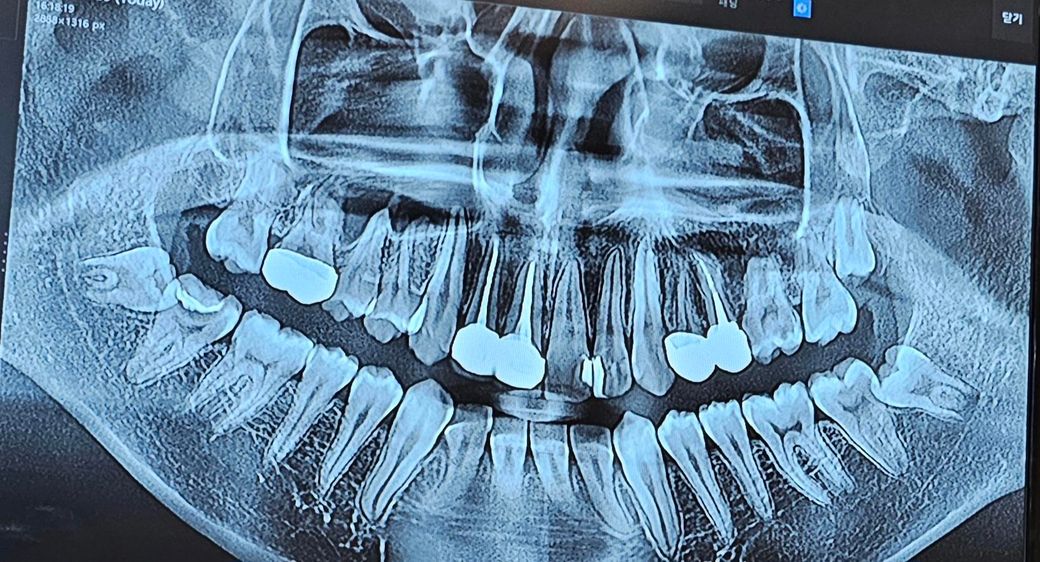

제 엑스레이 사진입니다 우선 엑스레이상으로 보이는 충치가 어디 이빨에 있는지 말씀 좀 부탁드립니다 바로 치료해야하는지도 말씀해주세요!

통증은 없습니다. 그래서 통증이 생기면 가거나 충치부위가 심하면 갈 생각이라서요..

위의 화질의 사진으로는 진단을 해드리긴 어렵습니다. 치료 받아야할 치아는 몇개 보입니다.

엑스레이 상으로 왼쪽 젤 뒤쪽치아에 충치가 잇을것같습니다. 치과에 가셔서 체크를 한번 받아보시는게 좋을것같습니다.

엑스레이 사진이 애매해서 확실히 여기에 충치가 있다 라고 할수는 없을 것 같습니다. 뭔가 의심되는 곳은 있지만 원본이나 작은 x-ray 사진, 육안으로 봐야 확인 가능합니다.

언제 찍은 사진인지는 모르겠지만 문제가 있었다면 찍었을 때 말씀해주셨을테고 그런것이 아니라면 우선 지켜보셔도 되겠습니다.